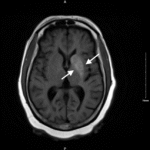

Nonketotic hyperglycemia hemichorea is a rare neurological manifestation associated with uncontrolled diabetes mellitus. This case report presents the clinical features, diagnostic workup, and management of a 74-year-old female with hemichorea secondary to nonketotic hyperglycemia. Patient presented to the emergency department with acute onset of right leg movement that was non-purposeful and random without any associated neurological symptoms such as paresthesias weakness, pain, or systemic symptoms. Patient’s medical history included untreated diabetes mellitus with glucose of 198 measured in the ED. Computed tomography of the and neck were unremarkable for any signs of ischemia, occlusion, hemorrhage or masses. Brain MRI without contrast showed T1 shortening within the left basal ganglia involving both the caudate nucleus and the lentiform nucleus, a radiologic finding common in nonketotic hyperglycemia hemichorea. Patient was admitted to the hospital for diabetes management. Patient’s symptoms did not completely resolve prior to discharge from the hospital but was closely monitored by her primary care doctor and neurologist; she had significant improvements in her symptoms over the subsequent year with improvement in her activities of daily living (ADLs).